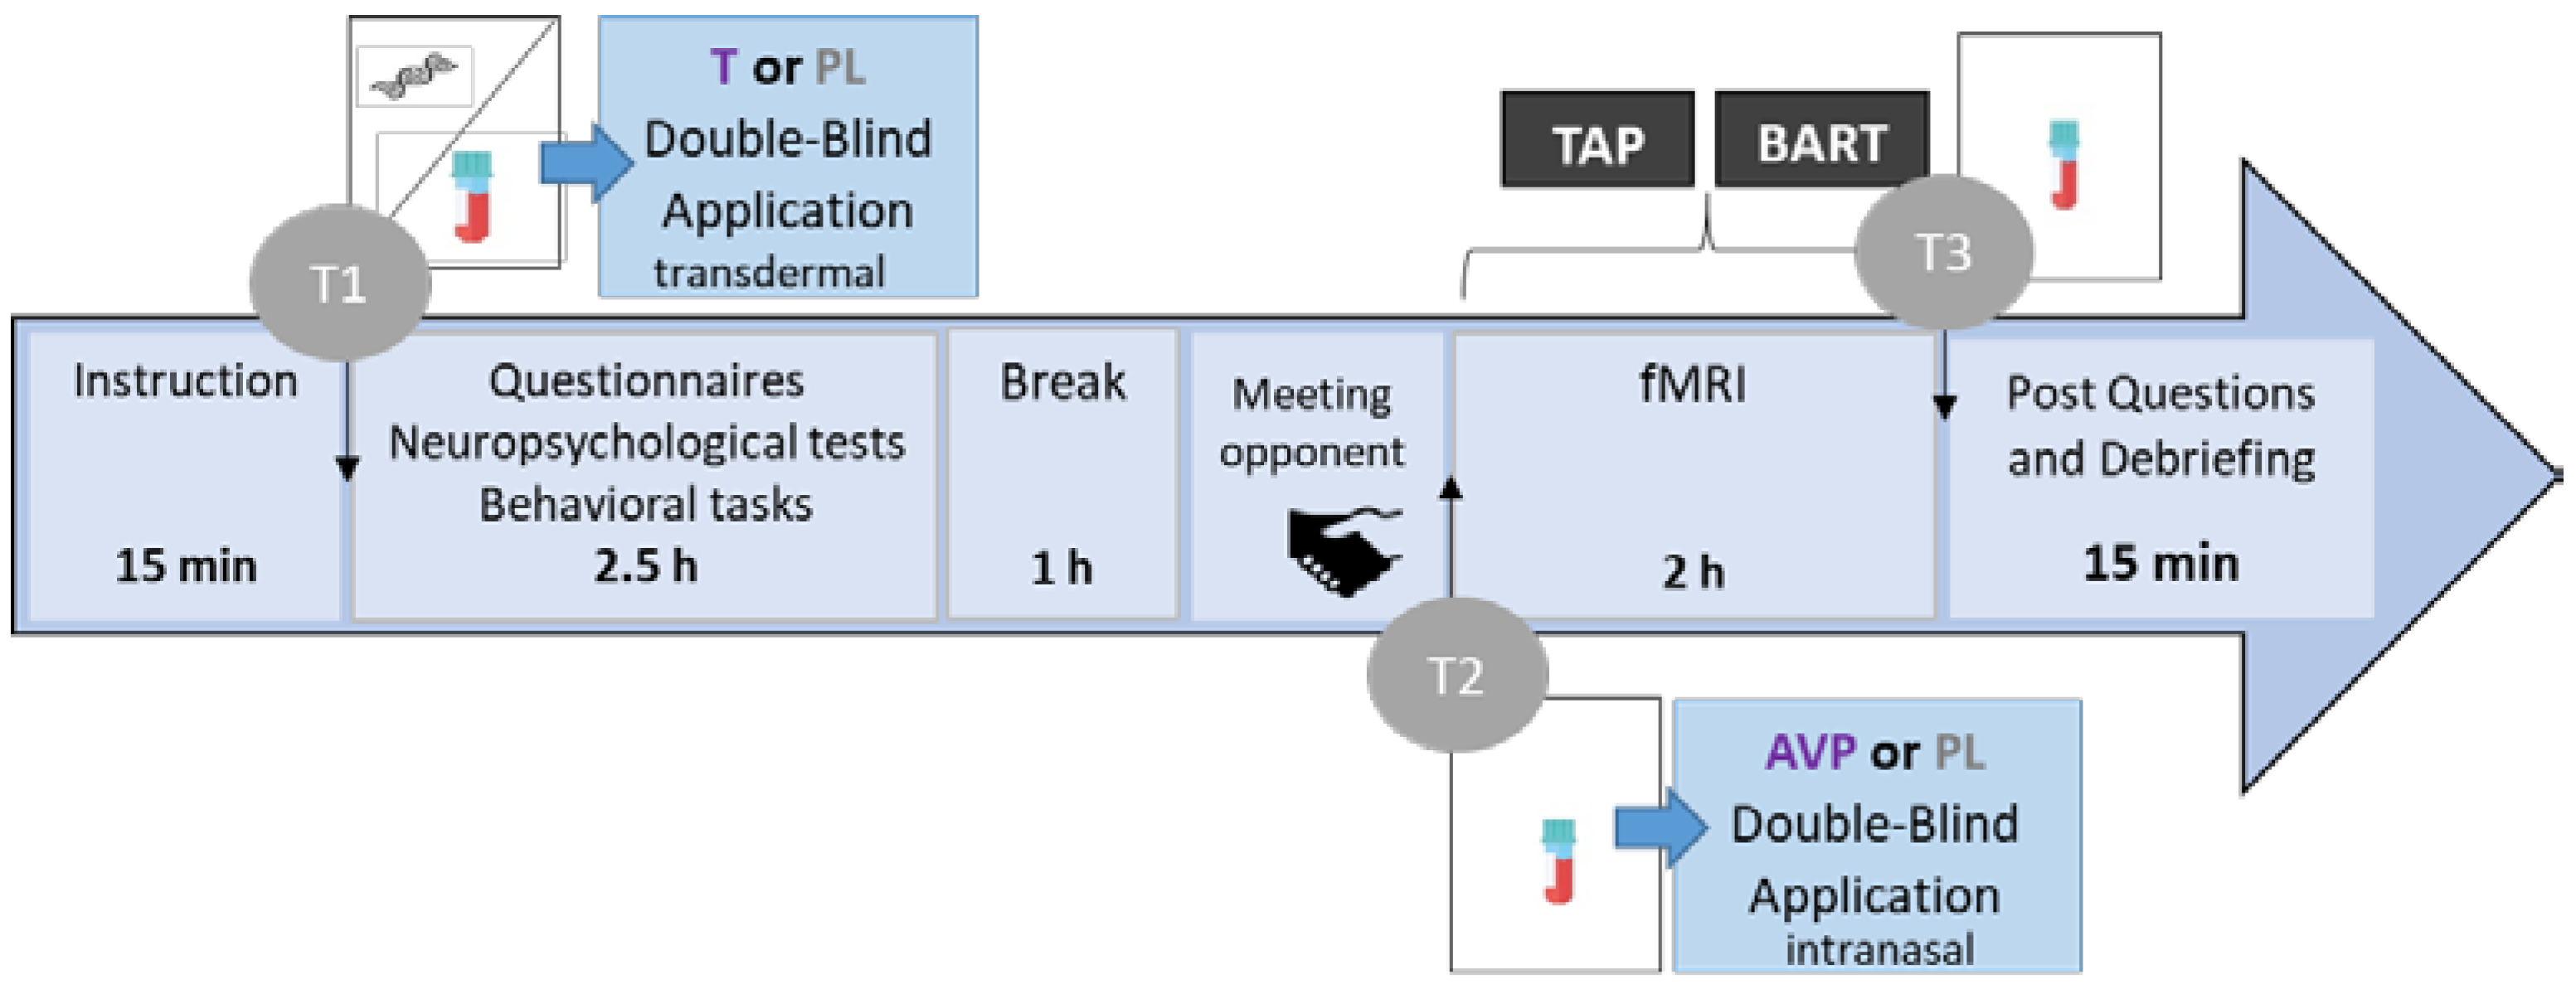

2.2. Procedure

2.3. Hormonal Levels

2.7.1. Hormonal Levels